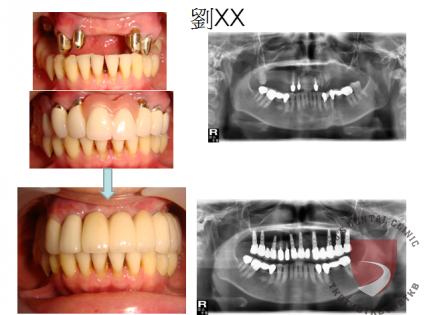

全口重建劉xx

成效因人而異,須遵從專業醫師指引